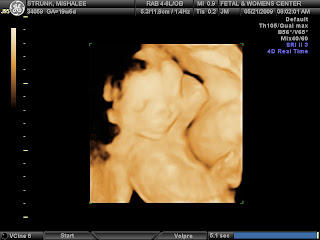

Absolutely no doubt that HE is all boy. We can't show you the proof, it's too graphic! Axel James Strunk's 20 week ultrasound looks a heck of a lot like his big brothers... he's long, string bean-ish, big feet and measuring bigger than his 20 weeks. They estimate him at 14 oz. with a due date of Sept. 30, BUT we've heard this before with Spanky and will stick with our EDD of 10-09-09

Lounging: